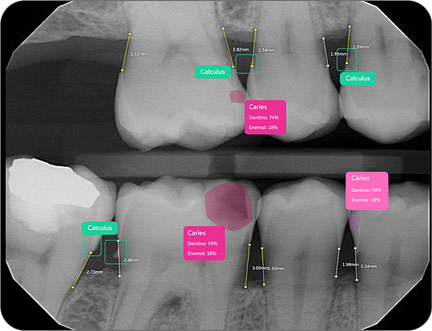

43% of caries go undiagnosed

20% of diagnosed caries aren't actually decay

49% of periapical lesions remain undetected

Pearl's Second Opinion AI system has demonstrated remarkable efficacy, with Ophir Tanz noting, "We pick up on average 37% more disease per radiograph encountered." This capability enables earlier intervention and more preventative care approaches.